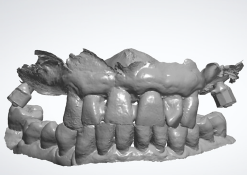

At the end of the surgical session, the position of the implants was defined by the use of specific scan bodies connected to each other through the use of the universal scan template. Then, the post-surgical digital scan was carried out, including the entire maxilla, the skeletal scan bodies, the implant scan bodies and the universal scan template (Figure 14).

Figure 14: Post-surgical digital scan including the entire maxilla, the skeletal scan bodies, the implant scan bodies and the universal scan template.

As seen in the previous case, in the resulting post-surgical intermaxillary space, a fixed full-arch temporary prosthesis was digitally designed and manufactured in a complete digital workflow (CAD/CAM) with the occlusal plane parallel to the Camper’s plane and the bipupillary plane, it was then screwed on the implants (Figures 15-22). The definitive prosthesis will be fabricated once the implants are integrated and both hard and soft tissue are healed and stable.

Figure 15: Maxillo-mandibular relationship in patient’s habitual occlusion in maximum intercuspation obtained matching the pre-surgical and post-surgical digital scans.